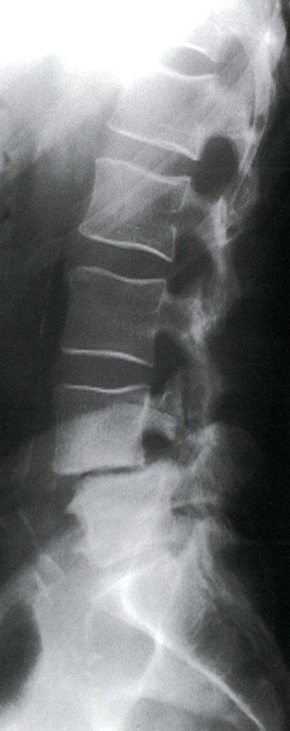

Modality X-ray lumbar spine (lateral view)

Findings Anterior displacement of L4 on L5 is visible. In addition, there is degenerative disk disease with narrowing of the L4–L5 disk space.

Diagnosis Disc Space Narrowing e.g. degenerative disc disease; Associated with endplate sclerosis and osteophytes